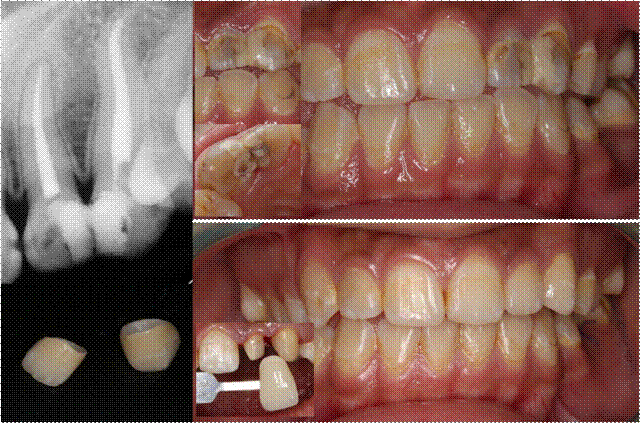

A3冷光美白技术是采用高强度蓝光,隔除有害的紫外线与红外线,将美白剂快速渗透至牙齿深层,与深层的色素发生置换反应,从而达到美白牙齿的效果。整个冷光照射仅需30分钟,美白剂不接触牙龈,对牙齿结构及牙釉质不会造成伤害。

冷光美白术对于着色牙、轻中度四环素牙、氟斑牙等具有很好的美白效果。

图:重度四环素牙的冷光美白(连续两次治疗效果)